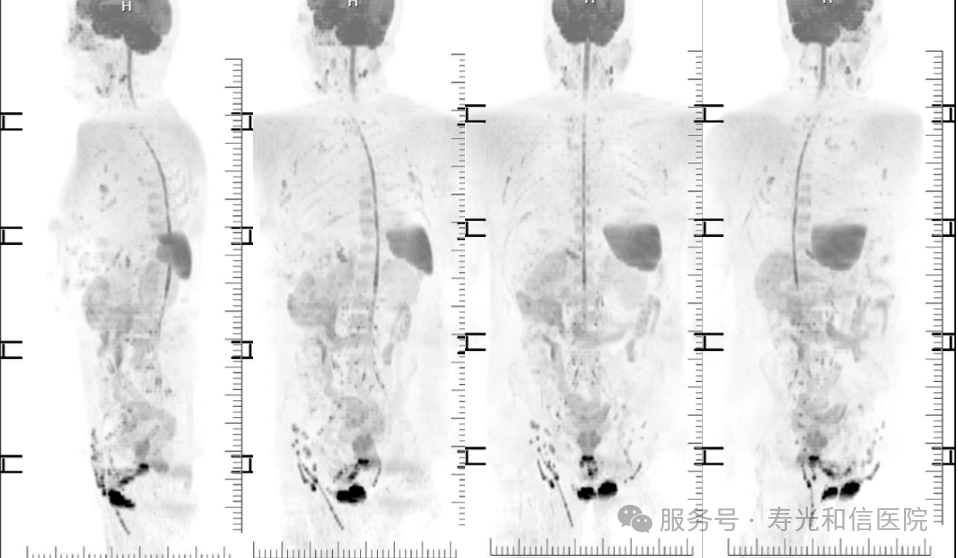

与PET-CT依赖放射性示踪剂、CT存在电离辐射不同,DWIBS完全基于磁场和射频波,无辐射风险,适合儿童、孕妇及需要多次随访的患者。对于有家族肿瘤史、携带致癌基因突变(如BRCA1/2)或长期接触致癌物的人群,DWIBS可作为无创筛查工具,帮助早期发现病变。在已确诊的肿瘤患者中,DWIBS可快速判断是否存在全身转移,指导分期和治疗方案选择。研究显示,其对骨转移的检出率与PET-CT相当。

(躯干类PET观察肿瘤转移情况)